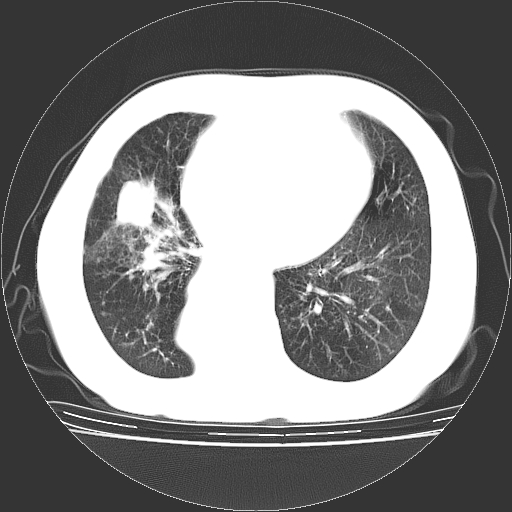

标题: CT23067:女,70岁,咳嗽、咳痰一个月,低热一周。 [打印本页]

女,70岁,咳嗽、咳痰一个月,低热一周。

1.左上肺结核,部分纤维化。右肺中下叶部分肺不张,内见液化、坏死及点状钙化,右中下叶支气管壁增厚、管腔狭窄,见多个点状钙化,结合临床考虑支气管内膜结核,建议痰检查抗酸杆菌并参考血沉。两肺多个小圆点状高密度灶,境界模糊,多考虑结核肺内播散。但本人年龄较大首先应支气管镜检以除外右肺癌。

一元论:内膜结核伴下肺阻塞性肺炎并双肺播散!另:主动脉夹层。右侧少量胸腔积液。

支气管内膜结核肺内播散.右侧少量胸腔积液.主动脉夹层.